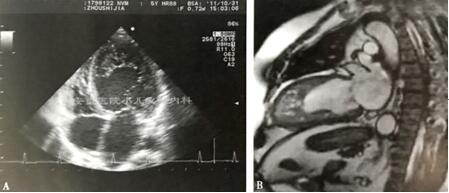

主要是无创检查:经胸Echo及CMR,但这两种方法的诊断标准目前仍有高度争议(图3)。经胸超声心动图易识别、应用广泛、费用低廉,仍是最常用的诊断方法。文献中常应用3种方法,1990年Chin首次提出量化致密心肌层与肌小梁层比值,以舒张末X/Y比值评价(图4)。2004年Stöllberger等提出另一诊断标准,强调了自左室心尖至乳头肌水平多于3条粗大肌小梁,收缩末NC>C,因未量化比值,故易诊断过度。近期大多LVNC临床研究主要采用的是Jenni等2001年提出的4项诊断标准,以收缩末非致密心肌层(non-compaction,NC)与致密心肌层(compaction,C)的比值大于2为主要诊断依据(图5)。

图3 超声和磁共振方法诊断心肌致密化不全 A.ALVNC超声心动图(四腔心切面);B. ALVNC磁共振(CMR)左室长轴位